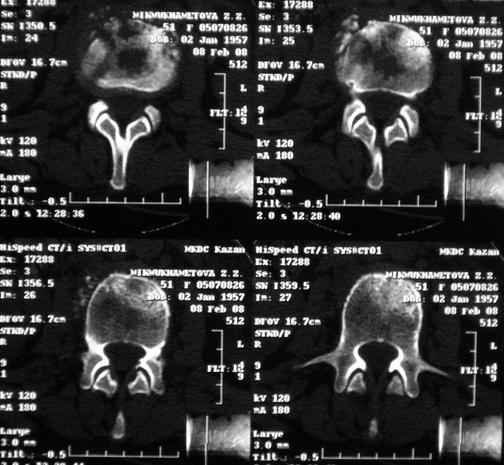

Отправляю MRI в динамике, снятые с пленки на фотоаппарат.

|

MRI через три недели

По данным представленных КТ и МРТ у больной имеется достаточно выраженная степень деструкции тел позвонков (около 30% общей костной массы тела позвонка), что определяет высокий риск возникновения патогических переломов и появления локальной кифотической деформации на этом уровне.

Судя по снимкам похоже идет речь о спинальном остеомиелите для диф диагноза стоит провести черезкожную пункционную биопсию(с помощью КТ)